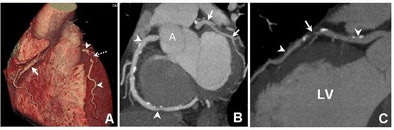

| A 40-year-old man who presented three hours after the onset of substernal chest pain had inconclusive initial evaluation in the emergency department; troponin was positive eight hours after presentation. Following CT angiography showing an 80% stenosis in the mid-left anterior descending artery, the patient underwent invasive coronary angiography, stenting. Images courtesy of Dr. Udo Hoffman. |